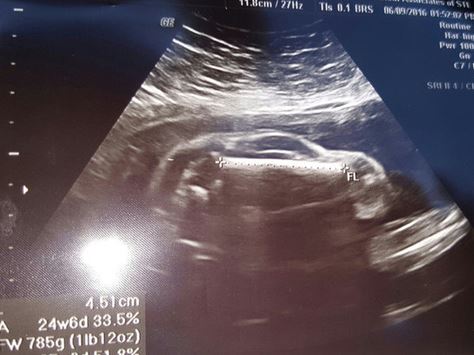

Una donna britannica, incinta alla 24esima settimana, si è recata dal ginecologo per un’ecografia al feto. L’immagine apparsa sul monitor ha lasciato tutti a bocca aperta. Quella che si intravede sembra una sagoma simile ad un’automobile. La foto è stata diffusa dal marito della donna su Reddit e ha attirato la curiosità di molti iscritti al social network.